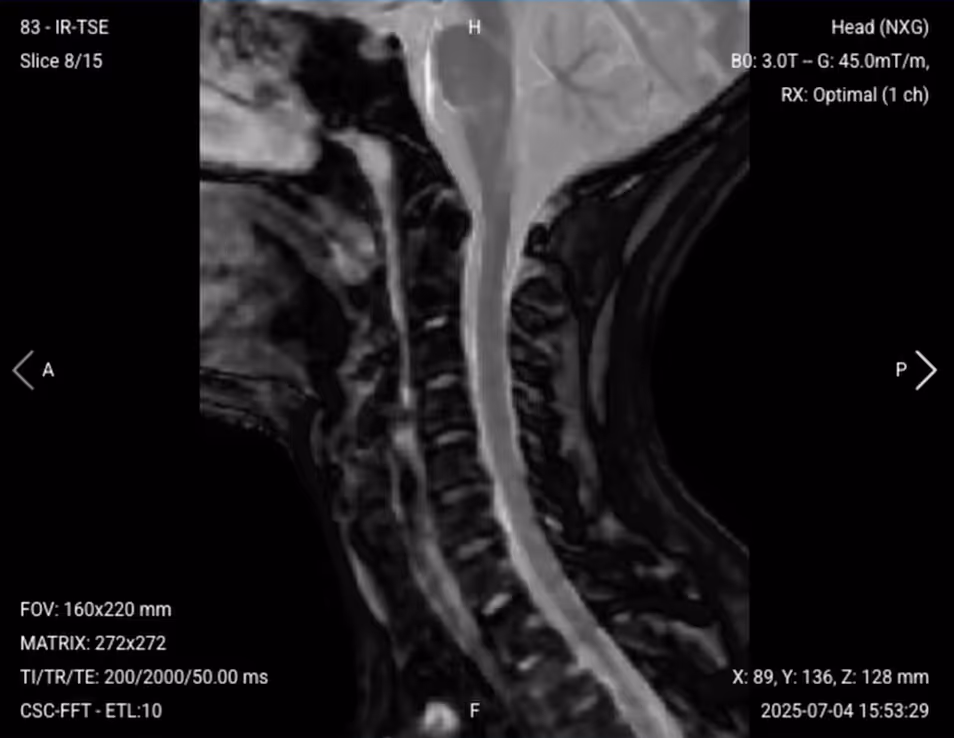

3. Planning Sagittal STIR TSE

✅ Correct Planning:

Correct planning of sagittal STIR TSE

Planning Instructions:

• Copy the slice geometry and planning from the previous sagittal T1 sequence.

• Keep the same slice angulation, coverage, and positioning to ensure images of different contrasts can be clearly compared.

STIR TSE – Clearest View of Fluid-Related Tissues and Conditions

STIR (Short Tau/TI Inversion Recovery) suppresses fat signals completely, which makes water-rich tissues stand out even clearer than with normal T2 TSE. This makes STIR ideal for detecting subtle fluid-related conditions – like edema, inflammation, and infections – where increased water content would otherwise be obscured by fat.

In the cervical spine, this contrast is particularly useful for identifying bone marrow edema, ligament tears, cord contusions, and infections like discitis or myelitis. STIR is crucial for detecting acute trauma injuries and inflammatory conditions where water content might not be visible on standard T2 sequences.

We capture STIR images in the sagittal plane to provide comprehensive assessment of inflammatory and traumatic changes.

Sagittal STIR TSE of the Cervical Spine – Correct Image Example:

Sagittal STIR TSE of the Cervical Spine – Correct Image Example

Things to Look for in Sagittal STIR:

• Fat should appear uniformly dark (well-suppressed).

• Look for bright signal in bones indicating marrow edema.

• Assess ligaments for tears or inflammation.

• Look for any inflammatory processes in soft tissues.

• Evaluate for cord edema or contusion.